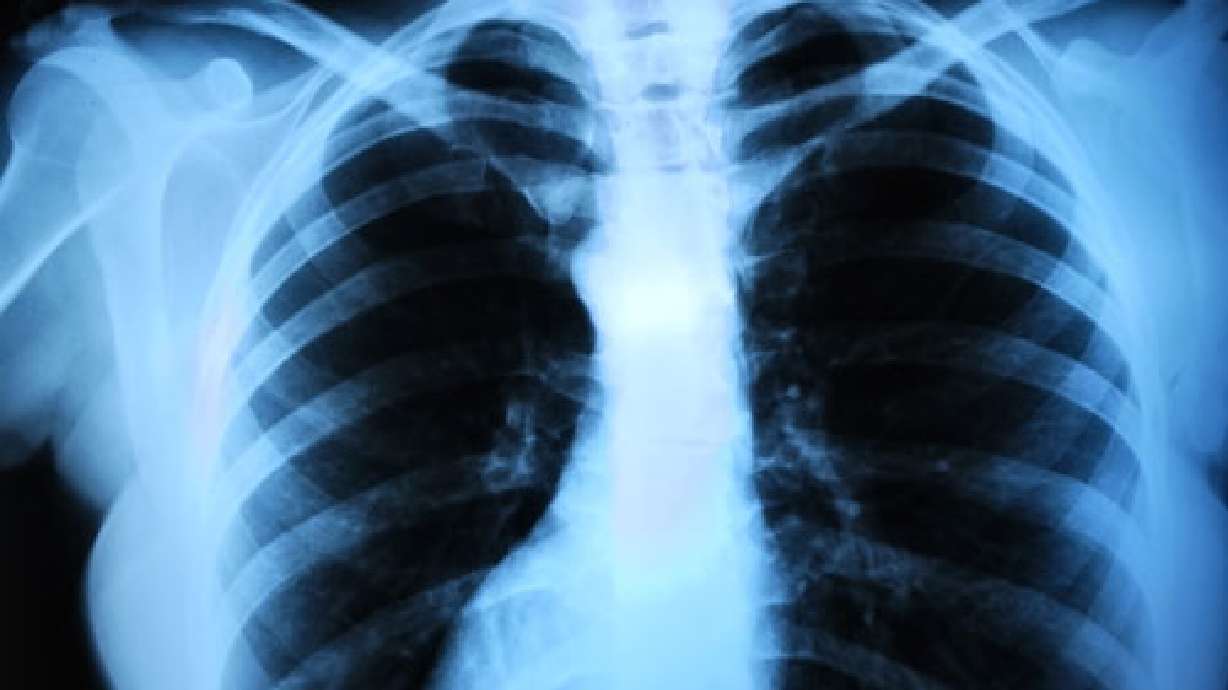

If your ribs are fractured, they will be tender to touch and you'll feel a sharp pain in your chest when you take a deep breath. The most common cause of a fractured rib is a direct blow to the chest, often from a car accident or a fall. Coughing hard can also fracture a rib.

It is important if you suspect broken ribs to consult a doctor first. This condition is worrisome due to the impact it can have on your general health. It will hurt to breathe deep, but not doing so can cause several things to happen: One, it will decrease your oxygen-carbon dioxide exchange causing you to have shortness of breath. Second, because you are not breathing deeply and coughing due to the pain, infection can set in quickly. Third, you could possibly have a collapsed lung, which could turn deadly very fast.